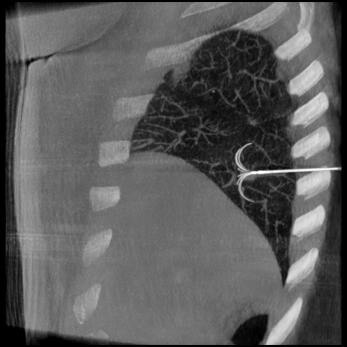

Tissus mous